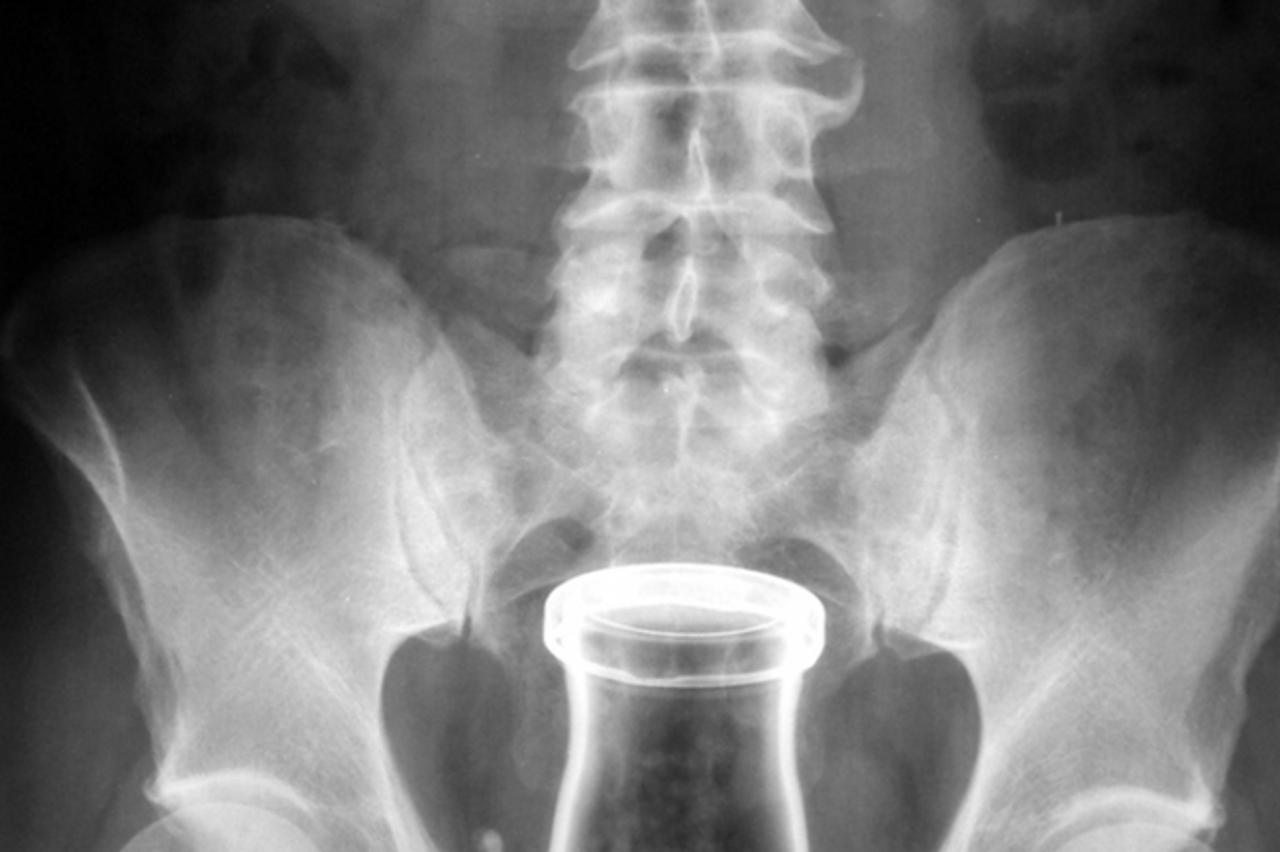

MR otkrio trend: Čep dezodoransa umjesto dijafragme

– Magnetska rezonancija u njezinoj je utrobi otkrila plastičnu čašicu – prisjeća se prof. Štern. Nakon što je izvađena, liječnica je prepoznala – poklopac dezodoransa.

Trag burne noći u zdjelici

– Nisam znala zašto ga je ugurala u vaginu, no mlađi kolege su me podučili: “Profesorice, djevojke to koriste kao bi se zaštitile od trudnoće?!” – prisjetila se prof. Štern. Smijući se svom neznanju, liječnica komentira: – Očito je djevojka imala burnu noć kad je poklopac iz vagine dospio čak u zdjelicu.